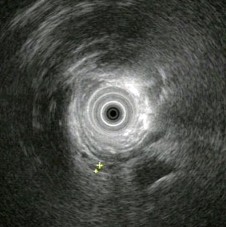

男,42岁,右上腹绞痛反复发作二年,此次发病三天,发冷,发热(38.9℃),查:巩膜明显黄染,超声内镜如图中病变可能的诊断是()。

A:正常

B:胰腺囊肿

C:慢性胰腺炎伴胰管结石

D:胰腺囊腺癌

E:胆总管结石伴扩张